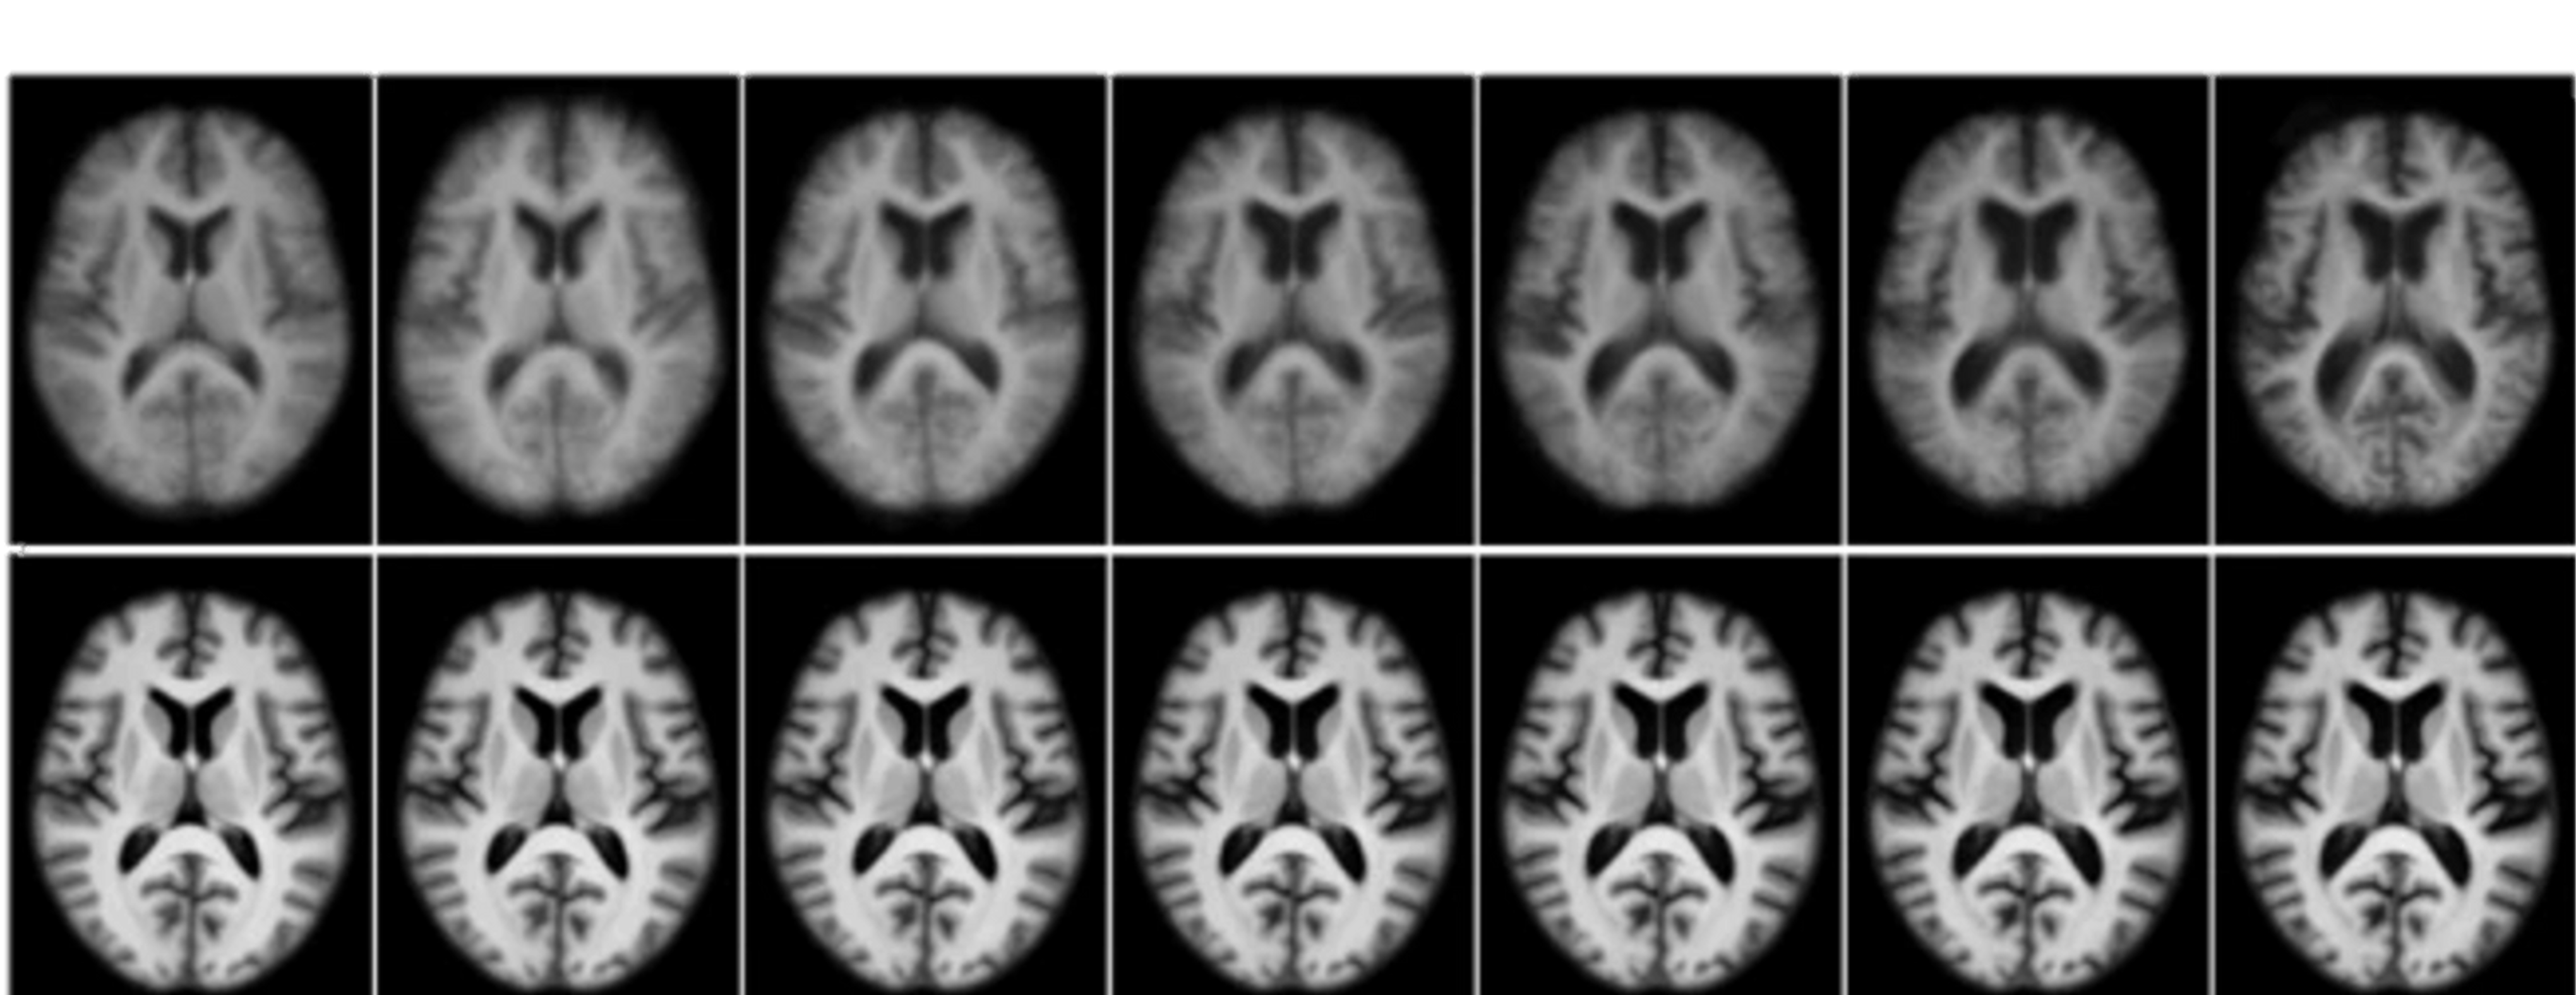

99.9% of drugs cannot penetrate the blood-brain barrier. We are changing that reality.

Only lipid-soluble molecules under 400 Daltons can cross the BBB passively. Most biologics are far too large for standard transport.

Our 4-10nm fibers bypass receptors entirely, inserting directly into leaflets for non-destructive, high-volume entry.

Contact with BBB endothelial cells triggers temporary pore formation, allowing rapid cytosolic entry without toxicity.